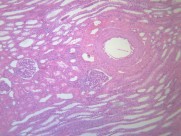

肾小管renal tubule 与肾小囊壁层相连的一条细长上皮性小管,具有重吸收(reabsorption)和排泌作用(secretion).肾小管按不同的形态结构,分布位置和功能分成三部分;近端小管,细段和远端小管。肾小管在肾髓质中。